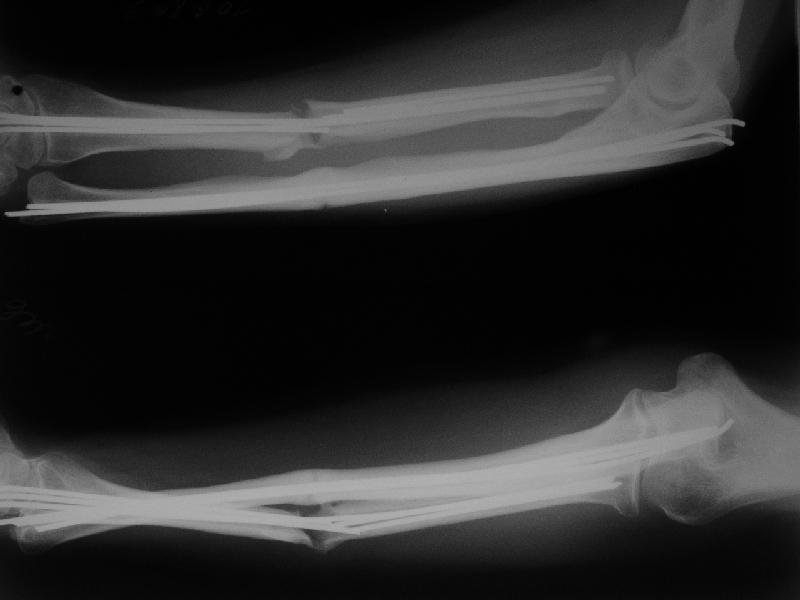

Уважаемые коллеги, Госпитализирована женщина, 31 год. Травма 26.09.06. Бытовая, упала. Оперирована в одной из горбольниц открыто, пучками спиц. 1 месяц в гипсе.

Подвижность усилилась примерно в 2 мес. (видимо, перелом спиц в лучевой кости). Движения в локтевом суставе N, ротация хорошая (подвижность лучевой кости), в кистевом тыльная 5-10 гр, ладонная 30гр. Обсуждаем варианты реостеосинтеза. Спицы удаляем все, при удалении из центрального отломка лучевой без вскрытия кости в области перелома не обойтись. Если восстановить ось и длину лучевой кости, получается дефект ~1,5-2 см. Замещать дефект удлинением одого из отломков в аппарате? Долго, и функция кисти и пальцев может еще ухудшиться.Поэтому думаем про укорачивающую резекцию обеих костей, локтевой чуть больше, остеосинтез пластинами, наверно, LCP. Блокируемый интрамедуллярный остеосинтезтоже доступен, но есть ли тут у него преимущества? Или есть смысл попытаться не трогать локтевую, а заместить дефект лучевой аутотрансплантатом из крыла? Или резецировать головку локтевой? Какие вариант и почему тут предпочтителен, на Ваш взгляд? Спасибо!Александр Виноградский клиника травматологии УНИИТО

1. У этой пациентки кость в принципе срастается, т.е. остеогенез не подавлен - периостальная реакция. Т.е. складывается впечатление, что кость хотела срастись, но ей не дали. Не создали словий. Скорее всего - из-за нестабильного остеосинтеза и несостоятельнйо гипсовой иммобилизации (видимо, виновата ротация). Отсюда вывод - создать эти условия. Для этого:

Ситуяция с диафизом лучевой кости по меньшей мере нормотрофическая. Видятся два плэйтерских подхода. Первый, менее перспективный, костно-пластческое удлинение луча+пластина. 2-й укорачивающая остеотомия локтя+ компрессионный пластинчатый остеосинтез обеих костей предплечья.